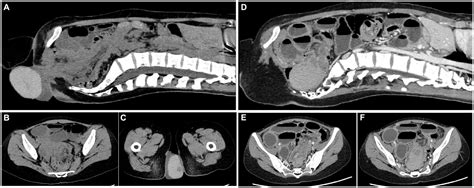

Getting a diagnosis for rectal prolapse is usually pretty straightforward, but it involves a few key steps to make sure your doctor understands exactly what’s going on. The first and most important part is usually a physical examination . Your doctor will likely ask you about your medical history, paying close attention to symptoms like straining, constipation, and any changes in your bowel habits. Then, they might ask you to strain as if you were having a bowel movement. This simple maneuver can often allow them to see or feel the rectal tissue protruding from the anus. They might also perform a digital rectal exam (DRE), where they insert a gloved finger into the anus to assess the tone of the anal sphincter muscles and to feel for any abnormalities or prolapse. This hands-on approach is often very revealing. If the prolapse isn’t apparent during the physical exam, or if your doctor needs more detailed information, they might order further tests. One common test is a defecography , which is a special X-ray that captures images of your rectum and anus while you’re having a bowel movement. This helps to visualize how well your rectum empties and to detect any internal prolapse or other issues. Another imaging technique that might be used is an anorectal manometry , which measures the pressure and coordination of your anal sphincter muscles. This can be helpful in understanding how well these muscles are functioning and if their weakness is contributing to the prolapse. In some cases, a colonoscopy might be recommended to rule out other conditions, such as polyps or cancer, or to assess the overall health of your colon. The goal is to get a clear picture of the extent of the prolapse, its severity, and any contributing factors so that the most appropriate treatment plan can be developed. So, don’t be shy, guys, these examinations are crucial for getting you the right help. Your doctor is there to guide you through it all.